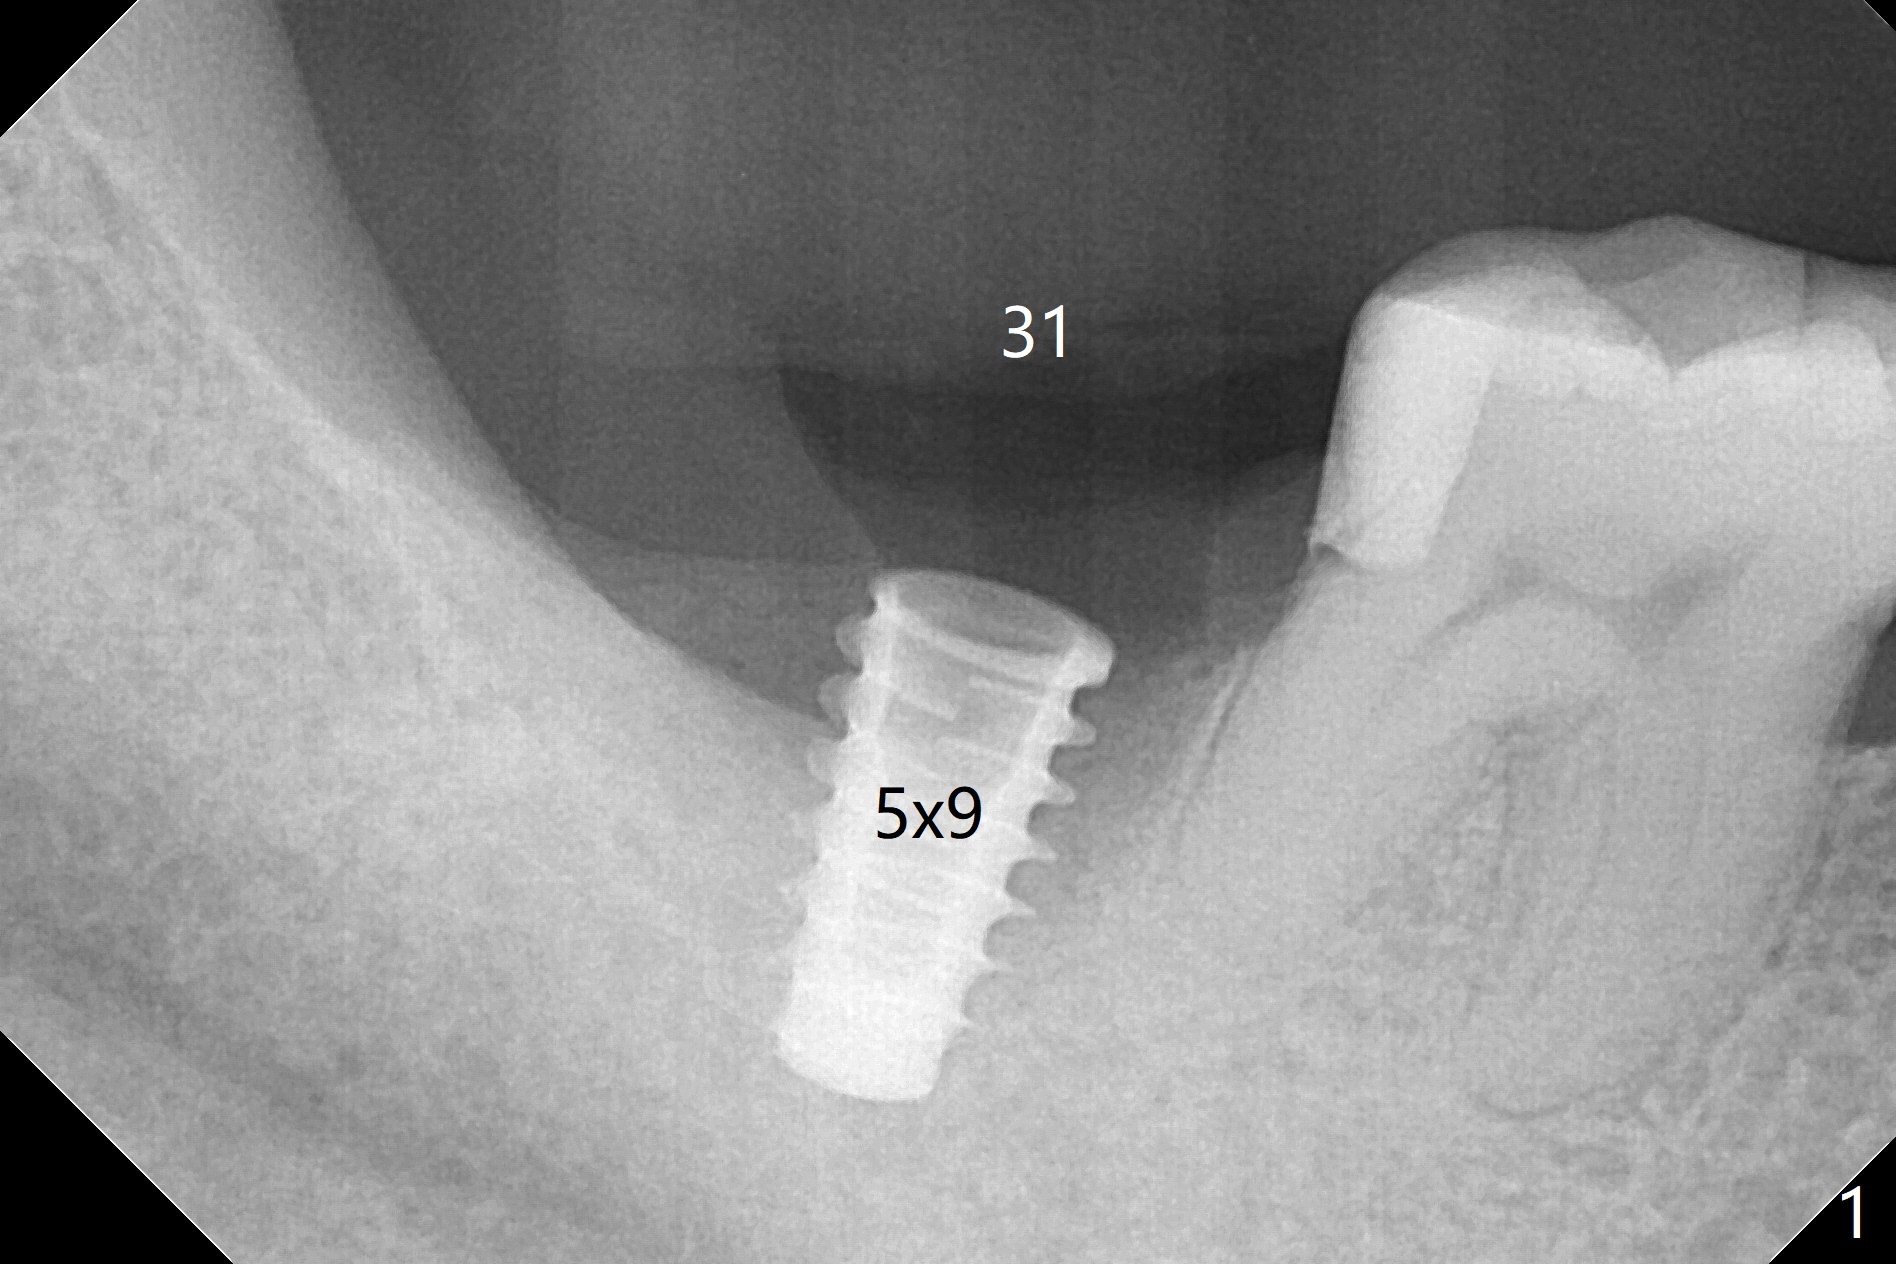

As expected, the buccodistal plate is low after extraction at #31. Osteotomy is initiated mesiolingually with 2 mm initial drill, 2.8 and 3.6 mm round drill with 4 mm stopper. The patient feels pain before the last drill reaches the depth. A 5x9 mm IBS dummy implant is placed with stability (Fig.1). When the definitive implant (5x9 mm) is placed, stability is lost. A 5.5x9 mm dummy implant achieves stability, while the definitive one loses stability. Increase in depth with 4.3 mm Magic Drill meets pain. Hemorrhage is another factor. When hemostasis is temporarily controlled, bone core is found. Nor removal of bone core with Final Drill or addition of allograft (Vera, .2-1.0 mm) in the osteotomy helps obtaining stability. Finally socket preservation is performed (Fig.2).